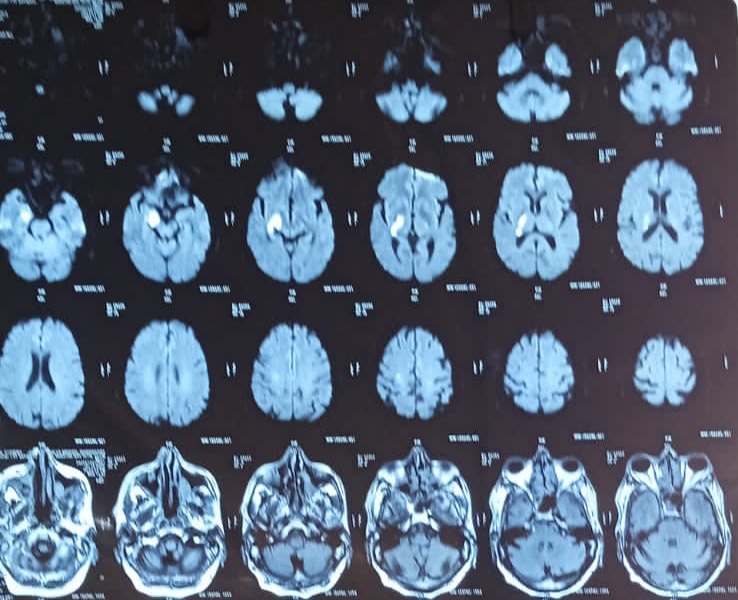

WEEK 1 : ARTERY OF PERCHERON INFARCT